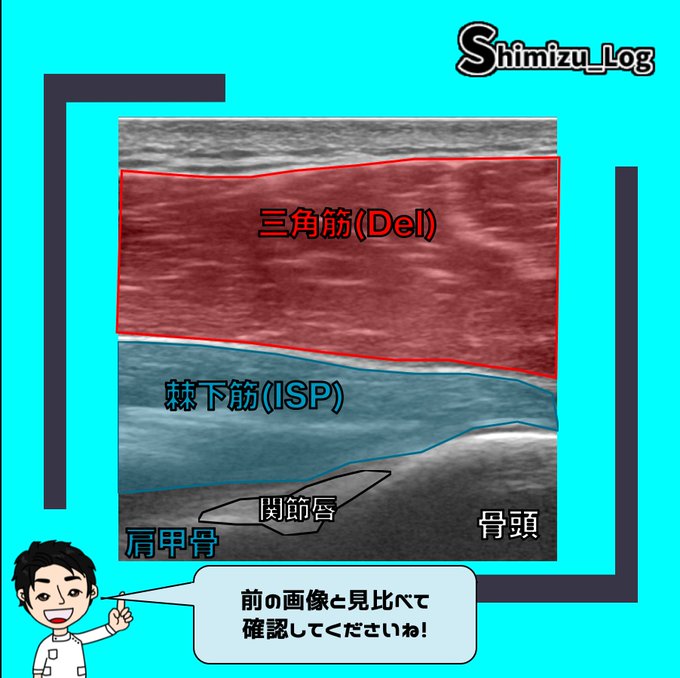

今日は『肩後面のエコー解剖』です

表層から深層まで各組織がどのような

位置関係になっているでしょうか?

スライドをすぐに進めるのではなく

一旦考えてから進んでくださいね^_^

立体的なイメージ

をできるようにしていきましょう!